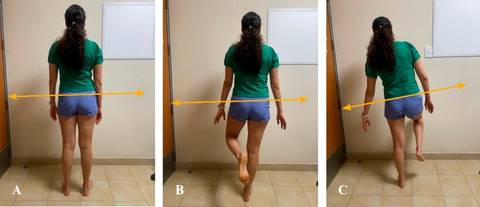

La marcha en paciente con coxalgia puede ser antiálgica y claudicante o bien secundaria a debilidad del grupo muscular antigravitatorio (pelvitrocantéreo), expresada como una marcha de Trendelenburg por debilidad de glúteo medio, en la cual la cadera se balancea en el plano coronal.2

Signo de Trendelenburg: se solicita al paciente el apoyo monopodal en cadera afectada; si ésta se balancea hacia el lado afectado, es indicativo de debilidad de glúteo medio (Figura 2).

Figura 2: A) Evaluación de simetría de extremidades inferiores. B) Competencia de glúteo medio para estabilidad pélvica en plano horizontal. C) signo de Trendelenburg positivo izquierdo, que indica insuficiencia de glúteo medio izquierdo.